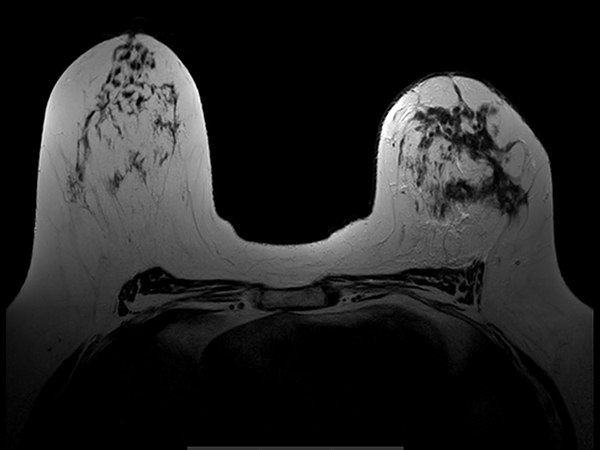

Axial T2w TSE